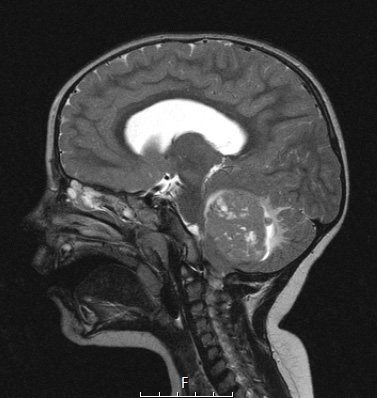

Washington University Experience | NEOPLASMS (EMBRYONAL) | Medulloblastoma, Histologically Defined | Extensive Nodularity (MBEN) | 5A2 Medulloblastoma, Desmoplastic (Case 5) T2 1 - Copy

5A2,3 T2-weighted images show numerous nodular hyperintense foci.